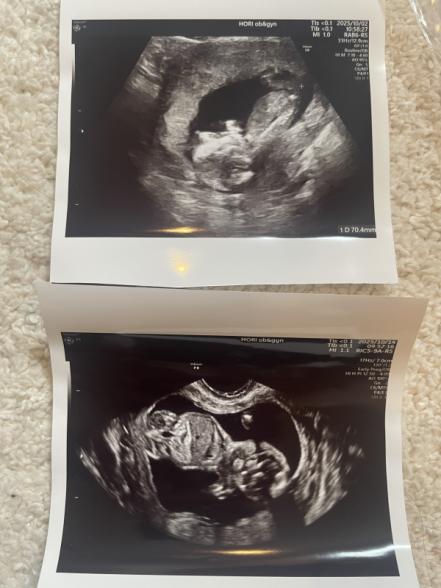

今回お腹の張りが気になり14w5dに急遽受診したところ68.9mmと言われました。

わかりにくいですがエコー写真添付しますので一度ご意見いただきたいです。